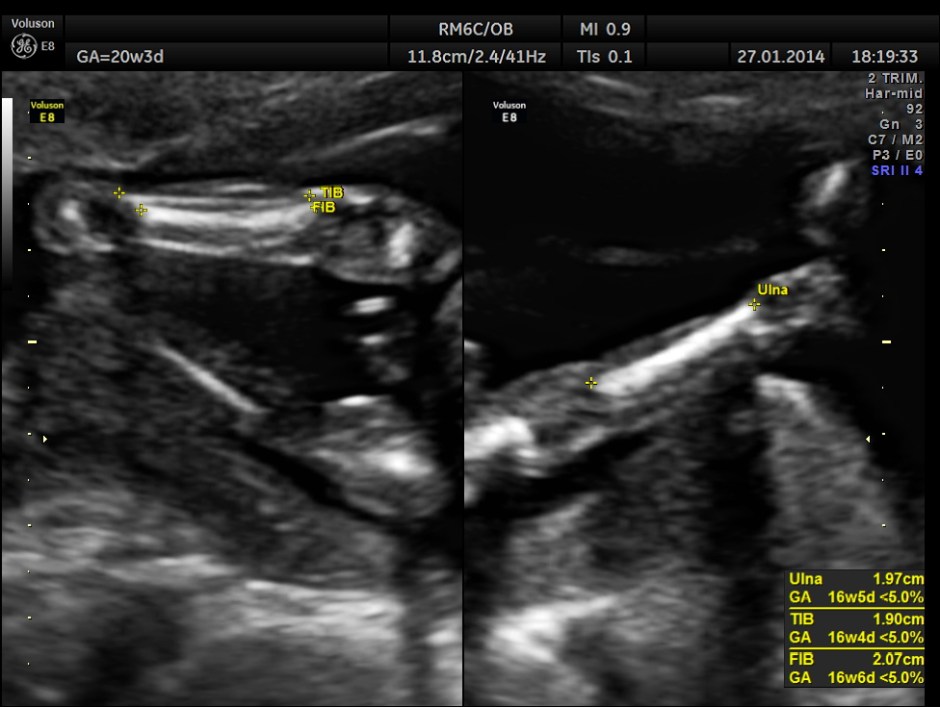

As it can be seen , the GA was around 20 weeks , but the AUA was around 17 weeks. All parameters – BPD, HC, AC, FL are < 2.3 %tile and all other long bones are < 5.0 %tile.